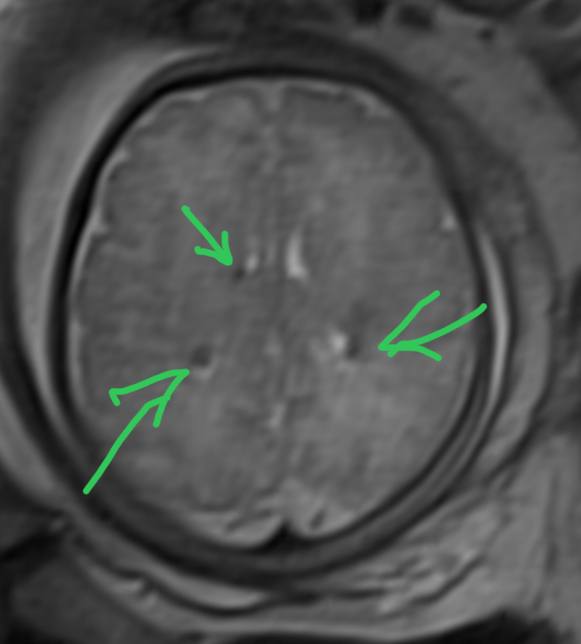

Подборка с рутины. Что видел за последние несколько дней.

Субэпендимальные узелки при туберозном склерозе у плода.

Мелкая липома четверохолмной цистерны.

Микроаденома гипофиза, которая видна только в раннюю постконтрастную фазу на динамическом сканировании.